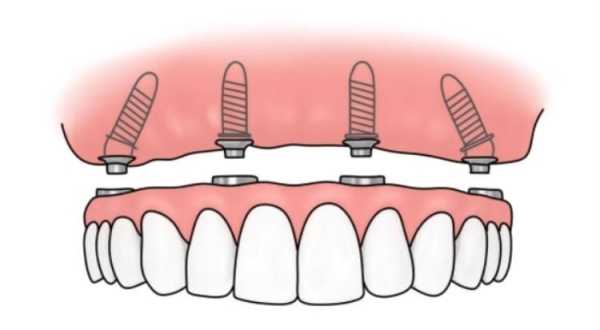

5、半口和全口種植牙費(fèi)用

半口種植牙價(jià)格一般在2萬元起,而全口種植牙價(jià)格通常在4萬元到10萬元之間。